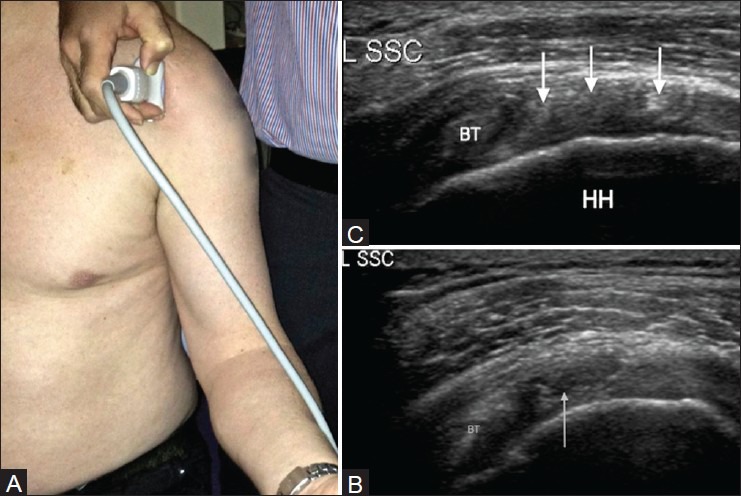

Por otro lado, la exploración en eje corto se realizará con el siguiente posicionamiento de la sonda:

En este eje, el corte de referencia que debes buscar en el ecógrafo es este: